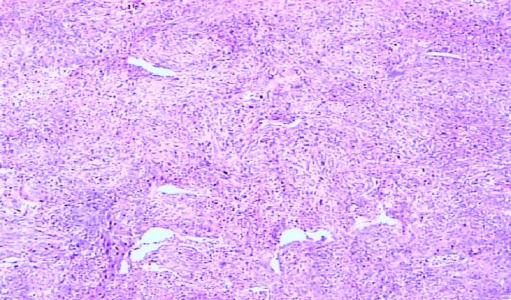

“当IHC信息被隐藏在CT图像上时,”首席研究员Jiabing Gu解释说,“通过使用纹理分析,可以辨别出这些信息与放射性组织之间的关系。”为了评估纹理分析是否可用于预测疑似甲状腺结节的IHC特征,来自中国济南大学的顾和同事招募了103名患者(训练队列与验证队列比例,?3:1)与疑似甲状腺结节的患者2013年1月至2016年1月进行甲状腺切除术和IHC分析。所有103例患者 - 男性28例,女性75例;中位年龄,58岁;范围33-70岁 - 在手术前接受CT,3D Slicer v 4.8.1用于分析手术标本的图像。为了便于重新测试方法,20名患者在10-15分钟内使用相同的扫描仪(LightSpeed 16,Philips Healthcare)和方案在两组CT系列中成像,无需对比剂给药。这些图像仅用于选择可再现和非冗余的特征,而不是用于建立或验证放射学模型。Kruskal-Wallis测试(SPSS v 19,IBM)用于改善纹理特征和IHC特征之间的分类性能。顾等人。考虑到p <0.05显着的特征,并且通过支持向量机方法训练基于特征的模型,评估准确性,灵敏度,特异性,相应的AUC和独立验证。从828个总功能中,选择了86个可重现和非冗余的功能来构建模型。细胞角蛋白19放射学模型的最佳性能在训练组中产生84.4%的准确度,在验证组中产生80.0%的准确性。同时,甲状腺过氧化物酶和半乳糖凝集素3预测模型在训练组中的准确率分别为81.4%和82.5%,在验证队列中分别为84.2%和85.0%。注意到细胞角蛋白19和半乳糖凝集素3水平在乳头状癌中很高,Gu坚持认为这些模型可以帮助放射科医师和肿瘤学家识别甲状腺乳头状癌,“这有助于早期诊断乳头状甲状腺癌并及时选择治疗方案。”